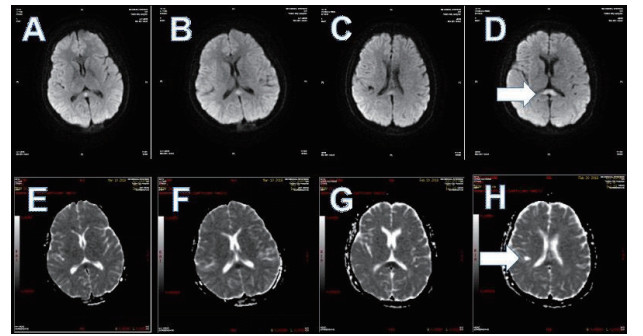

磁共振提示胼胝体局灶病变多为轻症患者(图 3);磁共振提示胼胝体双侧放射冠部散在病变多为中型患者(图 4);磁共振提示胼胝体双侧放射冠区弥漫性病变多为重症患者(图 5,6)。

| 图 5 重型患者,可见胼胝体双侧放射冠区弥漫性病变 |

| 图 6 重型患者,可见胼胝体双侧放射冠区弥漫性病变 |

总之,①磁共振明确氟乙酰胺的毒物靶点,进一步证实氟乙酰胺的作用机制为细胞毒性脑水肿所致脑白质脱髓鞘改变。②这种可逆性脑白质病变,可因中毒程度,轻症以胼胝体局部病灶为主,中度则为胼胝体散在病灶,重度则出现胼胝体为中心的广泛性病灶。③由于氟乙酰胺累及可逆性胼胝体压部病变综合征,属于可逆性病灶,因此本组患者应用激素冲击治疗均已取得良好预后。④对于原因不明的有阵发性痉挛发生或癫痫的患者,应该重点考虑行头部MRI检查,可协助排除是否是氟乙酰胺中毒。⑤重度中毒患者临床上可出现癫痫大发作,目前经头颅核磁检测可明确与其胼胝体广泛病灶相关联。